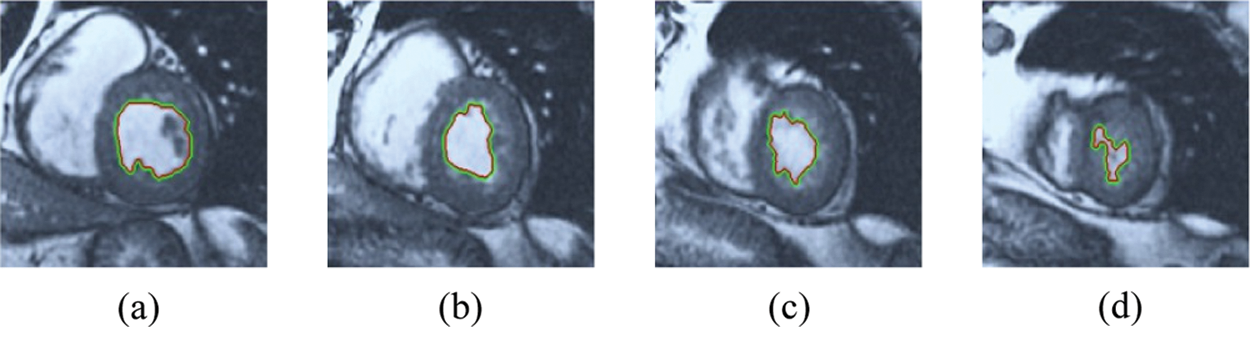

The BRW, HSRW, and ERW medical imaging segmentation schemes are executed on MATLAB, and examined on a short-axis of 3D multi-slices CMRI dataset [27]. Several segmentation performance metrics are utilized such as Dice Metric (DM), the Haussdorff distance (HS), and the Peak signal to noise ratio (PSNR). The BRW, HSRW, and ERW segmentation schemes are executed on a short-axis of 3D multi-slices CMRI datasets. The same multilayer CMRI dataset is segmented using various random walk methods. The presented results were obtained through using BRW, HSRW and ERW methods on five different groups of patients; each group contains 25 subject of multilayer CMR dataset. Experimental results illustrate that the BRW method can achieve a good segmentation of the LV cavity. The results of the HSRW algorithm have very comparable similarities to BRW, but with a slightly less efficiency and a much higher execution rate. Pre-calculations reduce the performance online time in offline mode. The average time of HSRW equals to 0.09 seconds for each slide. Raising the rate of K will improve the comparison and makes the process of segmentation more precise, but also reduces the execution time. The ERW technique results illustrate that this method has the greatest efficiency of segmentation. Figs. 5 to 7 show the resulting images of the BRW segmentation method on five sets of sample data. HSRW with pre-calculation segmentation method is applied on the same sets of sample data and illustrated in Figs. 8 to 10. Figs. 11–13 show the high efficiency segmentation using the ERW method with an earlier model for the same sets of sample data. The results of the Random Walk segmentation overcame the potential restrictions of the prior art CMR methods. The performance of segmentation is fast compared to segmentation methods based on edge and region. BRW precedes into account the properties of regions and edges, as shown in Figs. 5–7. Looking at the image as a graph, the technique makes it possible to integrate pixel relations with neighboring pixels. As a result, segmentation produces good quality BRW technique sections when their qualitative accuracy is compared to the ground truth, and this is also evident from the Tab. 1 measurements in the diastolic and systolic phases in Tab. 2 as well as in the complete cardiac cycle noticed. Figs. 8–10 illustrate the HSRW results. There are no dissimilarities observed in furthermost cases of CMR slides in the figures, but the correspondence measurements of the DM, PSNR and HS coefficients present that the results of the HSRW technique are worse than those of the BRW method. This presents that HSRW is an effective estimation of the random walk influence as mentioned in Tab. 1 and throughout the cardiac cycle in Tab. 2. The values of PSNR and DM are lower, whereas HS is higher than the BRW method, but with slight dissimilarities between HSRW and BRW methods throughout the blood circulation. The impact of execution eigenvectors pre-calculations is perfect when the execution time is faster than the BRW method and, in fact, more efficient than other segmentation method for LV heart segmentation. With the identical dataset, the ERW method shows a significant enhancement in efficiency, as presented in Figs. 11–13. From the scores, we can see that the segmentation is smoother and cleaner. The ERW method considers boundaries and areas, such as BRW, using the relations between adjacent pixels in the image. It also considers the additional regional advantage by including the assumptions that affect the results of the segmentation. Mean segmentation quality measurements are computed from the segmented images using correspondence measurements for instance DM, HS, and PSNR and verified for each method in the diastolic and systolic stages as presented in Tab. 1. Based on results, it can be determined that methods of random walk are enhanced in diastolic diagnosis and that their outcomes in the systolic stage are also of good efficiency. The results of the random walk segmentation methods in the complete blood circulation are shown in Tab. 2. The cardiac cycle similarity amounts indicate that DM and PSNR capacities of ERW are improved than the corresponding capacities in the case of the HSRW and BRW approaches; however, the HS measurements are lower than the equivalent measurements, as illustrated in Tab. 2. This designates that the ERW technique is the furthermost accurate segmentation technique among all the approaches stated above. The ERW technique has the uppermost value of PSNR, and the HSRW method has the lowermost value that denotes the uppermost speed in segmentation process.

Figure 5: BRW results for the first samples set

Figure 6: BRW results for the second samples set

Figure 7: BRW results for the third samples set